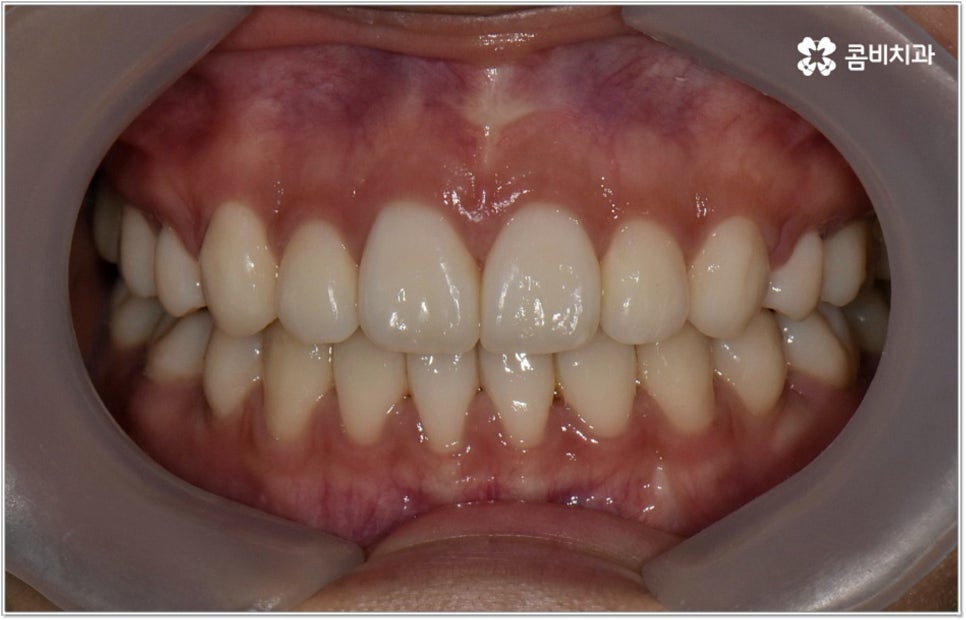

이러한 기능적인 부분 외에 심미적인 부분에서도 문제가 발생할 수 있는데요. 예를 들어 치아가 튀어나와 있다면 가만히 있어도 퉁명스러워 보이거나 화가 난 것처럼 느껴지고 입을 꼭 다물기가 어려워서 무리하게 힘을 주게 되기 때문에 입가나 턱에 주름이 질 수도 있어요. 이때 돌출입치아교정 치료를 받게 되면 위아래가 잘 맞물리는 가지런한 치열을 가지게 되는 것 뿐 아니라 자연스러운 입매와 부드럽고 균형잡힌 인상으로 바뀌게 되어 스스로 자신감 있는 태도를 가지게 되고 대인 관계에서 호감도도 높아질 거예요.